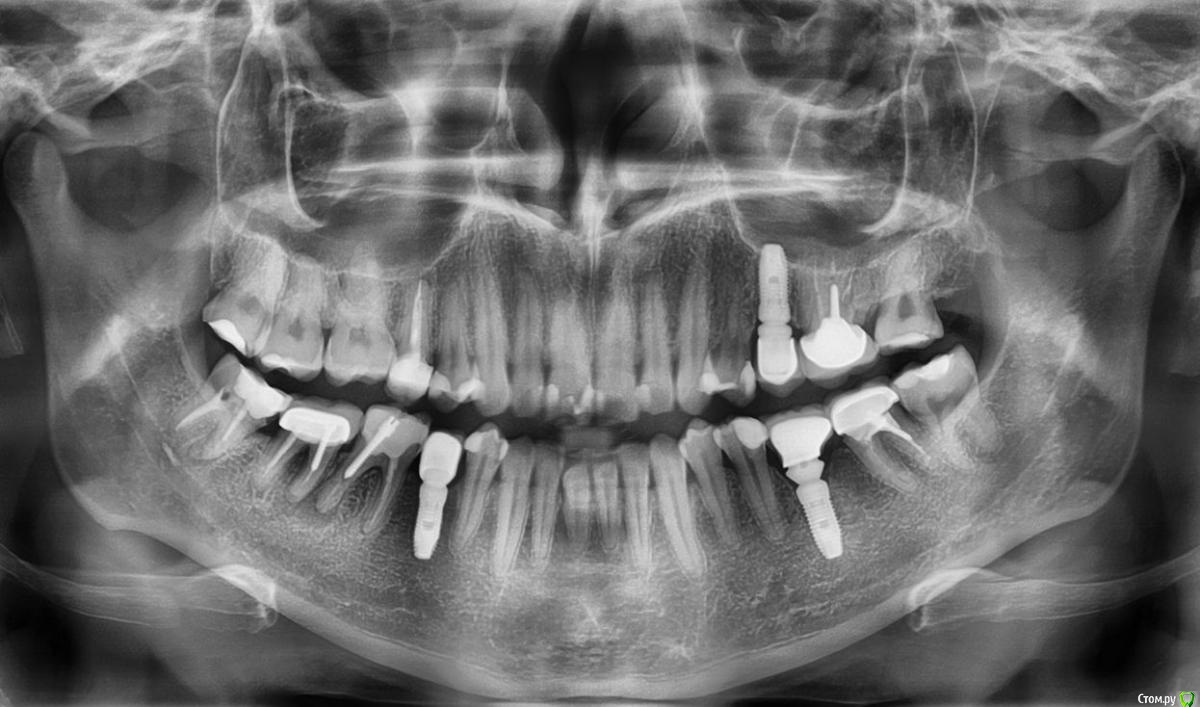

Izzum2009 Опубликовано 24 марта, 2015 Поделиться Опубликовано 24 марта, 2015 Здравствуйте!Прошу совета у специалистов. Подскажите, пожалуйста, что делать? 1. На 6-м зубе слева снизу, врач говорит, что киста, а на 7-м киста между корнями - это действительно так? На десне 6-го зуба вылез свищ (небольшой), я пила антибиотики неделю назад. Свищ прошел на несколько дней, а теперь вылез опять.2. Возможно ли избавиться от кисты без удаления этих 2-х зубов?3. Что скажите по остальному снимку? Заранее спасибо за ответы! Ссылка на комментарий

diesel87 Опубликовано 24 марта, 2015 Поделиться Опубликовано 24 марта, 2015 (изменено) Здравствуйте, при удачном извлечении анкерного штифта из канала, можно попробовать перелечить зубы, так же следующий восьмой зуб нуждается в перелечивании и семерка с другой стороны. Изменено 24 марта, 2015 пользователем diesel87 Ссылка на комментарий

Гарриевич Опубликовано 25 марта, 2015 Поделиться Опубликовано 25 марта, 2015 что качается 6го то он спасаемый однозначно, а вот с 7 надо найти причину "кисты" между корней и решать 1 Ссылка на комментарий

Izzum2009 Опубликовано 25 марта, 2015 Автор Поделиться Опубликовано 25 марта, 2015 На десне 6-го зуба вылез свищ Извините, ошиблась. Это на десне 7-го зуба свищ. Усугубляет ли ситуацию то, что на нем (на 7) стоит коронка - метеллокерамика? На 6-м нет свища. Здравствуйте, при удачном извлечении анкерного штифта из канала, можно попробовать перелечить зубы, так же следующий восьмой зуб нуждается в перелечивании и семерка с другой стороны.А что с восьмеркой слева и с семеркой справа не так?Давным-давно на восьмерке слева мне пломбировали каналы и задели нерв, потом я 3 месяца ходила с онемевшей губой и подбородком (как при анестезии). После этого появилось то горизонтальное белое пятно под корнями (это на всякий случай), если вдруг оно притягивает на себя внимание. Правильно ли я понимаю, что необходимо аккуратно извлечь штифты из 6 и 7-го зубов и просто перелечить каналы? Или врач по каналу опустится вниз "под канал" и удалит как-то кисту? Допустим, 7-ку пролечили и все хорошо. Коронку старую уже не поставить обратно, ее как-то распиливают, наверное, чтобы снять? Ссылка на комментарий

Гарриевич Опубликовано 25 марта, 2015 Поделиться Опубликовано 25 марта, 2015 коронку старую обратно не приспособить)да, правильно поняли, штифты убрать, все перелечить и "киста" сама пройдет Ссылка на комментарий